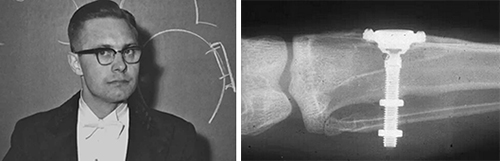

年轻时期的Brånemark教授和兔胫骨中植入的纯钛装置

1952年, Brånemark借鉴1950年剑桥大学一项研究技术,利用纯钛目镜植入兔子胫骨观察骨髓腔内微血管血流状态。几个月实验结束后,他发现钛制目镜与兔胫骨组织异常牢固的结合到一起,形成一个整体,难以取出。对此,Brånemark进行了一系列研究,将毕生精力致力于钛与人体组织关系的研究。